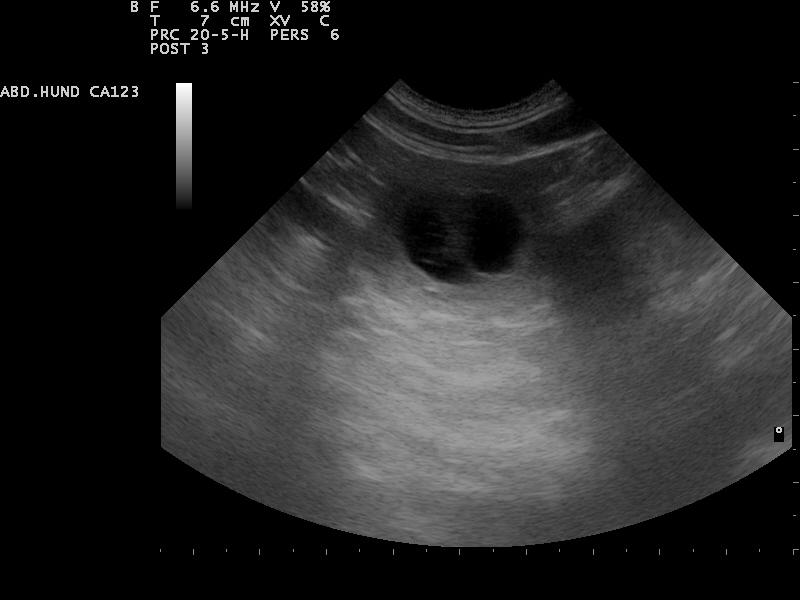

Hierfür eignet sich sehr gut die Gabe von Welpenfutter. Zu diesem Zeitpunkt kann mit einer Ultraschalluntersuchung

der Zustand der Trächtigkeit festgestellt werden. Besprechen Sie mögliche Risiken einer solchen Untersuchung mit dem Tierarzt.

Am 01.07.2014 waren wir zur Ultraschalluntersuchung und konnten

die ersten Bilder unserer Welpen bewundern.